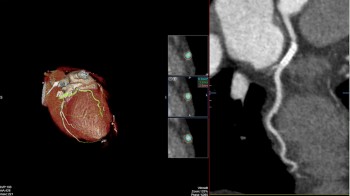

- MSCT koronarografija (prikaz krvnih žila srca CT-om, bez neugodnosti i komplikacija koje nosi klasična koronarografija), u saradnji s Poliklinkom dr.Al-Tawil